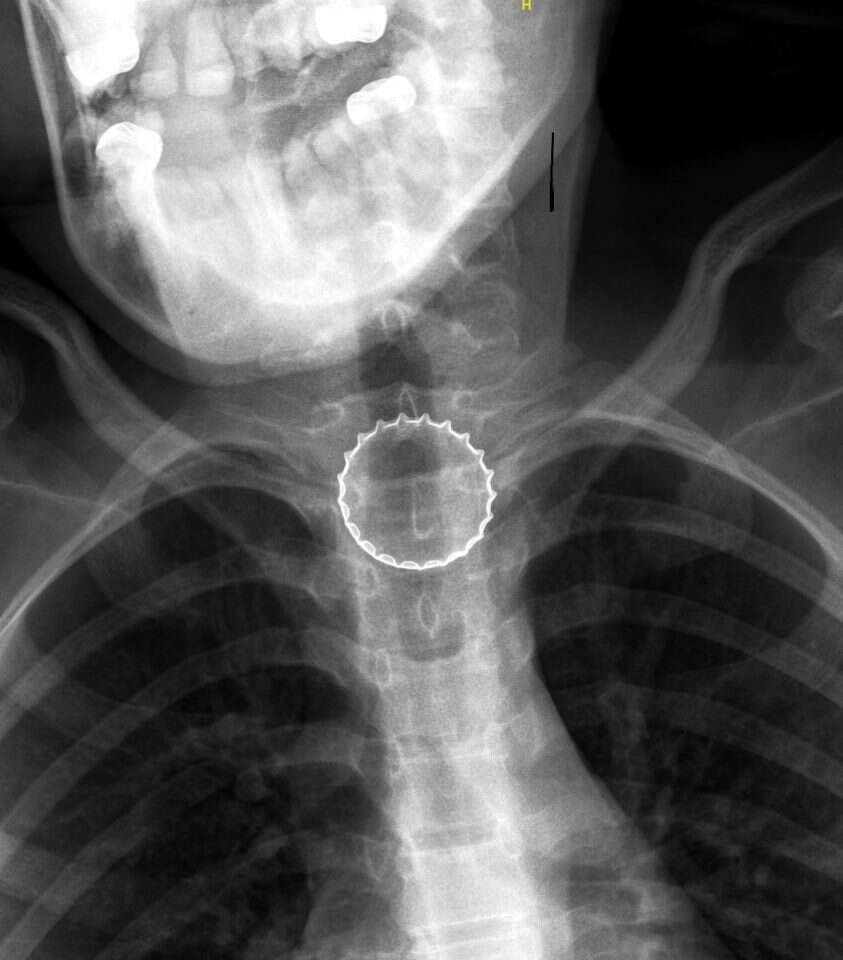

במיון ילדים עברה הנערה בירור מקיף ויסודי ע"י צוות בראשות ד"ר עלי ח'טיב, מומחה ברפואת ילדים, ובין השאר בוצע לה צילום רנטגן, בו התגלה גוף זר בוושט. הנערה הוכנסה לחדר ניתוח, שם – באמצעות ציוד אנדוסקופי ייעודי – הוצא מצינור הוושט פקק של בירה קורונה ע"י צוות ממחלקת אף אוזן גרון וניתוחי ראש-צוואר, בניהולו של ד"ר אייל סלע. הנערה אושפזה להשגחה למשך יממה ושוחררה במצב טוב.

ד"ר נתנאל איזנבך, רופא מתמחה במחלקת אף אוזן גרון, סיפר כי במהלך ההליך הניתוחי התברר, כי מעל לגוף הזר הצטברו שאריות מזון שונות, דבר שהקשה על תהליך הוצאת הפקק.

מנהל יחידת אף אוזן גרון ילדים במרכז הרפואי, ד"ר מעיין גרובר: "לנערה היה מזל שהפקק הגיע לוושט ולא לדרכי הנשימה, דבר שהיה עלול לגרום לחנק מיידי. יחד עם זאת, חשוב לדעת שגם כאשר גוף זר נתקע בוושט, זה עלול להיות מסוכן, במיוחד כאשר יש לו קצוות מחודדים כמו במקרה הנוכחי. הדבר עלול לגרום לקרע בוושט ולזיהום מסכן חיים בצוואר ובבית החזה".